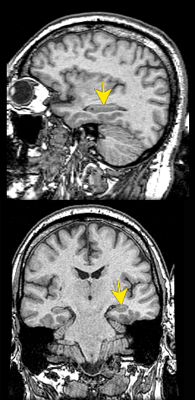

![]()

L'hippocampe est indispensable à la mémoire de travail.

L'hippocampe est également impliqué dans la

reconnaissance spatiale chez le rat (

infos).

L’information semble transiter par l'hippocampe avant d'être

transférée dans les aires corticales.